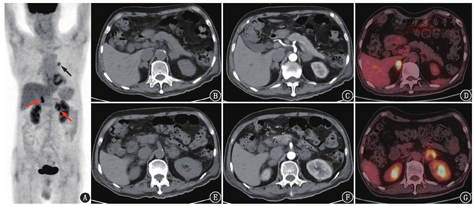

患者男,73岁,2021年6月开始自觉肤色加深,无其他不适,未诊治。2021年8月因外伤于外院查腹部平扫CT发现双侧肾上腺不规则肿物,左侧为著。后就诊于本院,血促肾上腺皮质激素(adrenocorticotropic hormone, ACTH)>1 250(正常参考值范围,下同:0~46) ng/L,皮质醇35.9(110.5~616.3) nmol/L。腹部增强CT及18F-FDG PET/CT显像(图1)提示右侧肾上腺弥漫增粗,增强后呈轻度均匀强化,代谢明显增高,SUVmax 7.0;左侧肾上腺见类圆形团块,大小约3.3 cm×3.7 cm,呈轻度不均匀强化,代谢呈不均匀增高,SUVmax 5.6,中心见代谢减低的囊变坏死区;此外,左肺门见一代谢轻度增高的小结节,大小约1.2 cm×1.6 cm,SUVmax 3.8,考虑可能为炎性淋巴结。